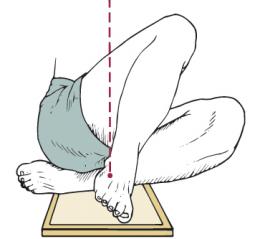

sisemine põikisuund istudes (lamades)